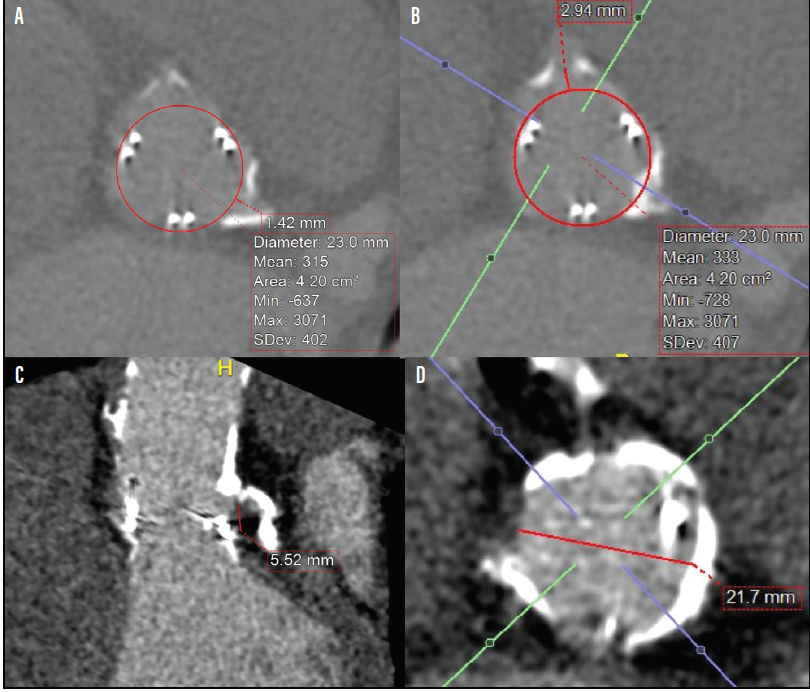

Dr. Cheung: I think all ViVs should go through the same evaluation process, specifically in terms of preoperative imaging. This preoperative imaging should include an aortogram to assess coronary flow and potential obstruction (Figure 1). Additionally, all patients should undergo a CT scan of their aortic root to measure the height of the left coronary artery (Figure 2), the height of the right coronary artery in relationship to the surgical valve, and also the virtual transcatheter heart valve (THV) to coronary (VTC) distance, the sinotubular junction, and also to the aortic wall and it is important to know whether the sinus is large enough to accommodate the expansion of the surgical valve (Figure 2).1,2

Figure 2. CT assessment of aortic ViV of a 23-mm Sapien 3 TAVR valve (Edwards Lifesciences) into a 23-mm failed Magna Ease pericardial valve. Risk of coronary obstruction is certain with the virtual transcatheter heart valve (THV) to coronary (VTC) distance < 4 mm, low coronary height, and narrow sinotubular junction (STJ). VTC distance to the left main ostium is measured at 1.42 mm (A). VTC of 2.94 mm to the right coronary ostium (B). Left main height of 5.52 mm from the base of the bioprosthesis (C). STJ diameter of 21.7 mm (D). Courtesy of Anson Cheung, MD.